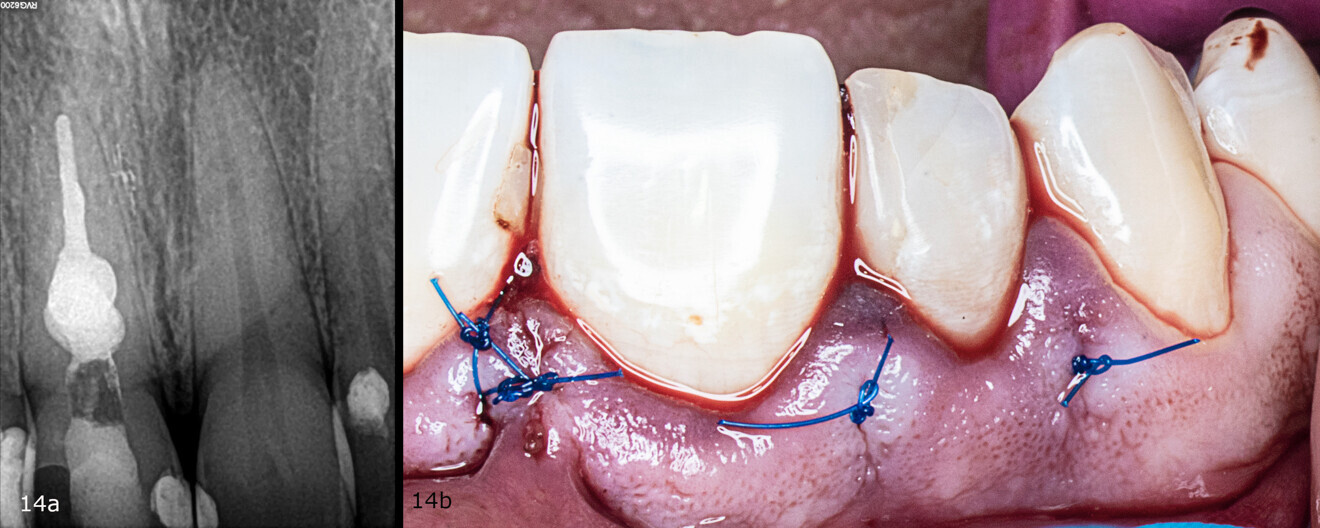

Figs. 14a & b: Radiograph taken after obturation (a). Clinical situation after suturing (b).

The obturation of choice was warm vertical compaction of gutta-percha and sealing with the AH Plus sealer (Dentsply Sirona). The resorption cavity was filled with a fast-setting mineral trioxide aggregate (Harvard Dental), the coronal part of the root canal was filled with warm gutta-percha and collagen sponge was placed (Figs. 12a & b; Figs. 13a & b). The flap was repositioned and sutured, and the tooth was restored with the GRADIA composite resin (GC; Figs. 14a & b, Fig. 15).

Recall appointments was performed after two (Figs. 16a & b) and four years (Figs. 17a & b). The radiographic examination showed the presence of bundle bone. The periodontal status was stable, and the tooth remained asymptomatic.